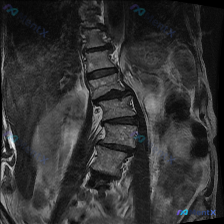

整理到一份腰椎影像资料,有点意思,也有点容易踩坑。 先放核心影像表现(腰椎矢状位T2WI): 1. L2/L3、L3/L4椎间盘信号尚可,L4/L5、L5/S1 T2信号明显降低(黑盘征); 2. L4/L5、L5/S1椎间盘后缘突出,明显压迫硬膜囊,相应节段脑脊液间隙变窄/消失; 3. 腰椎生理前...

整理了一份影像分析资料,先给大家看核心信息: - 给出的是 腰椎MRI T2序列矢状位 - 用户提示的观察重点是:脊柱侧弯 - 影像明确报了这些: - L4/L5、L5/S1椎间盘退变(黑盘征、高度变窄) - 这两个节段椎间盘向后突出,硬膜囊前缘受压 - 同节段椎管狭窄倾向 - 部分终板T2信号增高...

整理了一份腰椎MRI的影像分析资料,先抛出来大家讨论下阅片思路。 基础影像发现(先列客观的): - 腰椎多节段椎间盘T2信号减低(黑盘征),L2-L3到L5-S1都有 - L4-L5椎间隙变窄,椎间盘明显后突,硬膜囊受压很明显,椎管也窄了 - L5-S1也有椎间盘后突压迫硬膜囊 - 腰椎生理前凸变直...

整理了一份病例资料,有点意思: - 主诉提的是 Scoliosis(脊柱侧弯) - 但只给了 腰椎MRI-T2加权像(矢状位) - 影像上能看到: - L4/L5、L5/S1 节段椎间盘T2信号明显减低,髓核脱水退变 - 相应节段椎间隙高度有丢失 - 椎间盘向后突出,尤其是L4/L5、L5/S1水平...